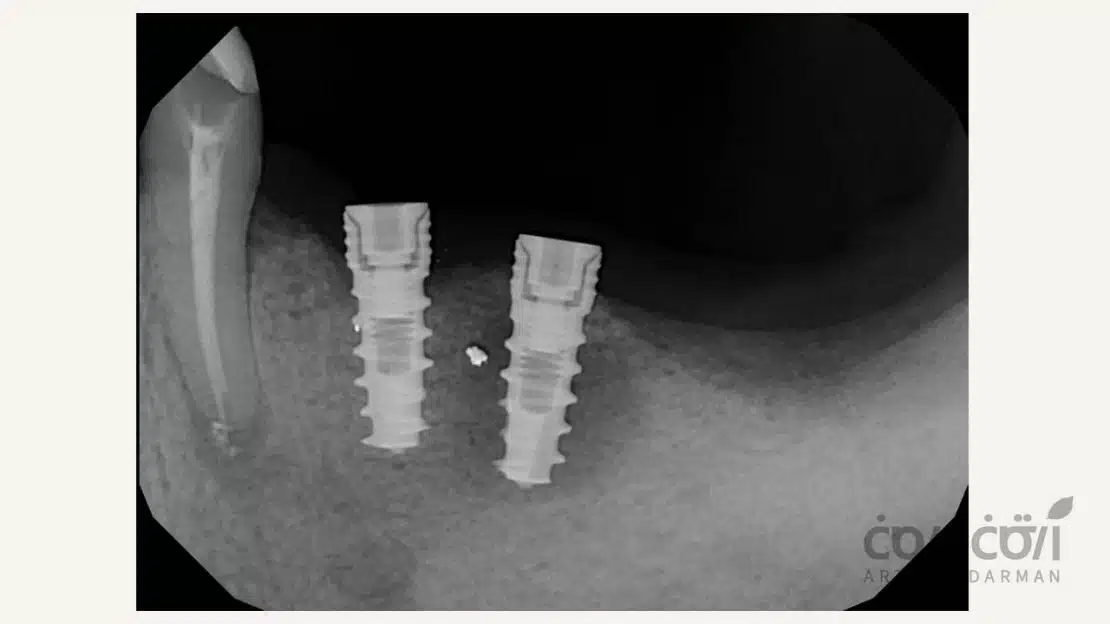

میکرو جا به جایی ایمپلنت

یکی دیگر از عوارض بالقوه ایمپلنت دندان، میکرو جا به جایی است. این وضعیت به حرکت بسیار کوچک ایمپلنت در محل کاشت گفته می شود که معمولاً چند دهم میلیمتر است و ممکن است در ابتدا بدون علامت باشد. میکرو جا به جایی میتواند به دلیل کیفیت پایین استخوان، فشارهای زودهنگام ناشی از جویدن یا تکنیک نامناسب جراحی رخ دهد و در صورت شدید بودن، احتمال شکست ایمپلنت را افزایش دهد. پیگیری منظم دندانپزشکی و رعایت توصیههای مراقبتی پس از جراحی، از مهمترین راهکارها برای پیشگیری و کاهش اثرات این عارضه است.